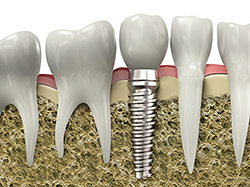

implantsIf you have missing teeth, it is crucial to replace them. Without all your teeth, chewing and eating can destabilize your bite and cause you discomfort. When teeth are missing, your mouth can shift and even cause your face to look older. Implants are a great way to replace your missing teeth, and if properly maintained, can last a lifetime!

An implant is a new tooth made of metal and porcelain that looks just like your natural tooth. It’s composed of two main parts: One part is the titanium implant body that takes the place of the missing root, and the second part is the tooth-colored crown that is cemented on top of the implant. With periodontal treatment, you can smile confidently knowing no one will ever suspect you have a replacement tooth.

In addition to tooth replacement, implants may be used to anchor dentures, especially lower dentures that tend to shift when you talk or chew. For patients with removable partial dentures, implants can replace missing teeth so you have a more natural-looking smile.